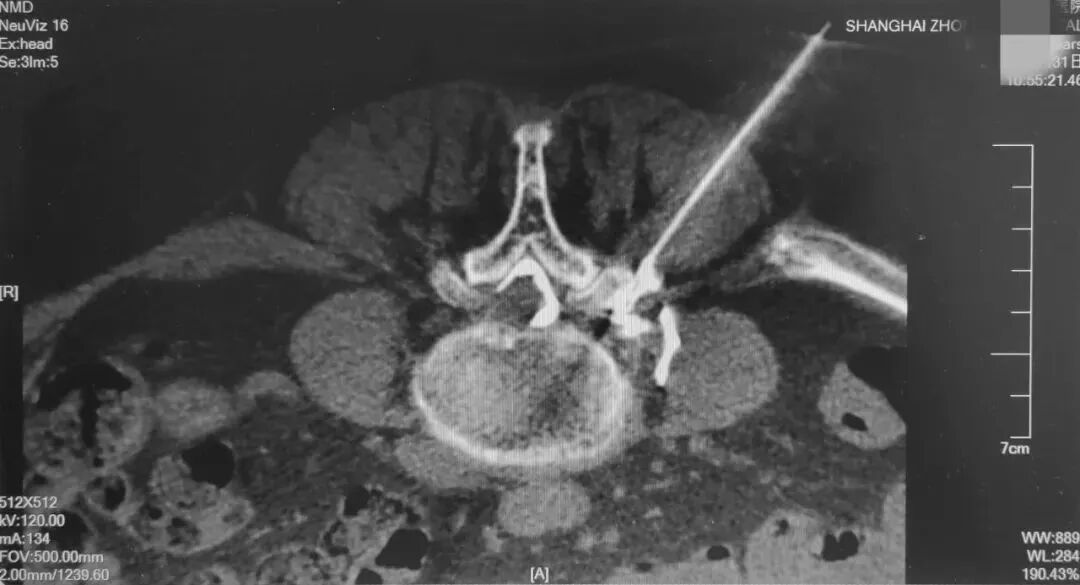

选择性神经根阻滞术,是在CT引导下将穿刺针经椎间孔穿刺到病变神经根处,将最少量的药物注射到病变神经周围,发挥最大的药效,对缓解神经根性疼痛有显著疗效。

椎间盘射频消融术,是将特定穿刺针,通过C臂机引导到突出的椎间盘内,使局部髓核组织产生高温后皱缩,椎间盘内压降低,突出物回缩,从而治疗椎间盘突出的技术。

爱钻研的看这里——手术医生先是通过C臂机确认进针点,穿入穿刺针后,通过“可视化”超声实时引导穿刺针的进针路线,发现路径有误可及时调整,同时多普勒超声也能发现路径内的血管神经,最大程度的避开重要组织,最终到达椎间盘的靶点处。再次通过C臂机确认针尖位置,行椎间盘造影,诱发出术前症状后,连接射频电极,对髓核组织进行消融。缓慢退出穿刺针至椎间盘外,此时针尖位置在受损神经根处,将少量药物注入后,拔出穿刺针。